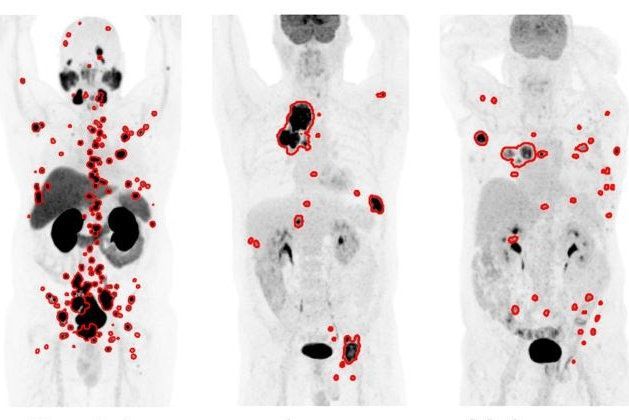

An AI PET/CT tool accurately segments tumors for multiple cancers, according to research presented at #SNMMI24. buff.ly/4aQDWPO #RadiologyAI #ImagingAI #NuclearMedicine #radiology @SNM_MI